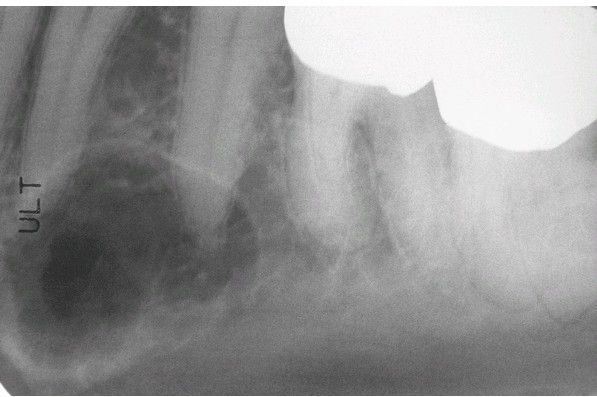

Intrabony Venous Malformation

. Well-circumscribed radiolucency that contains fine trabeculations.